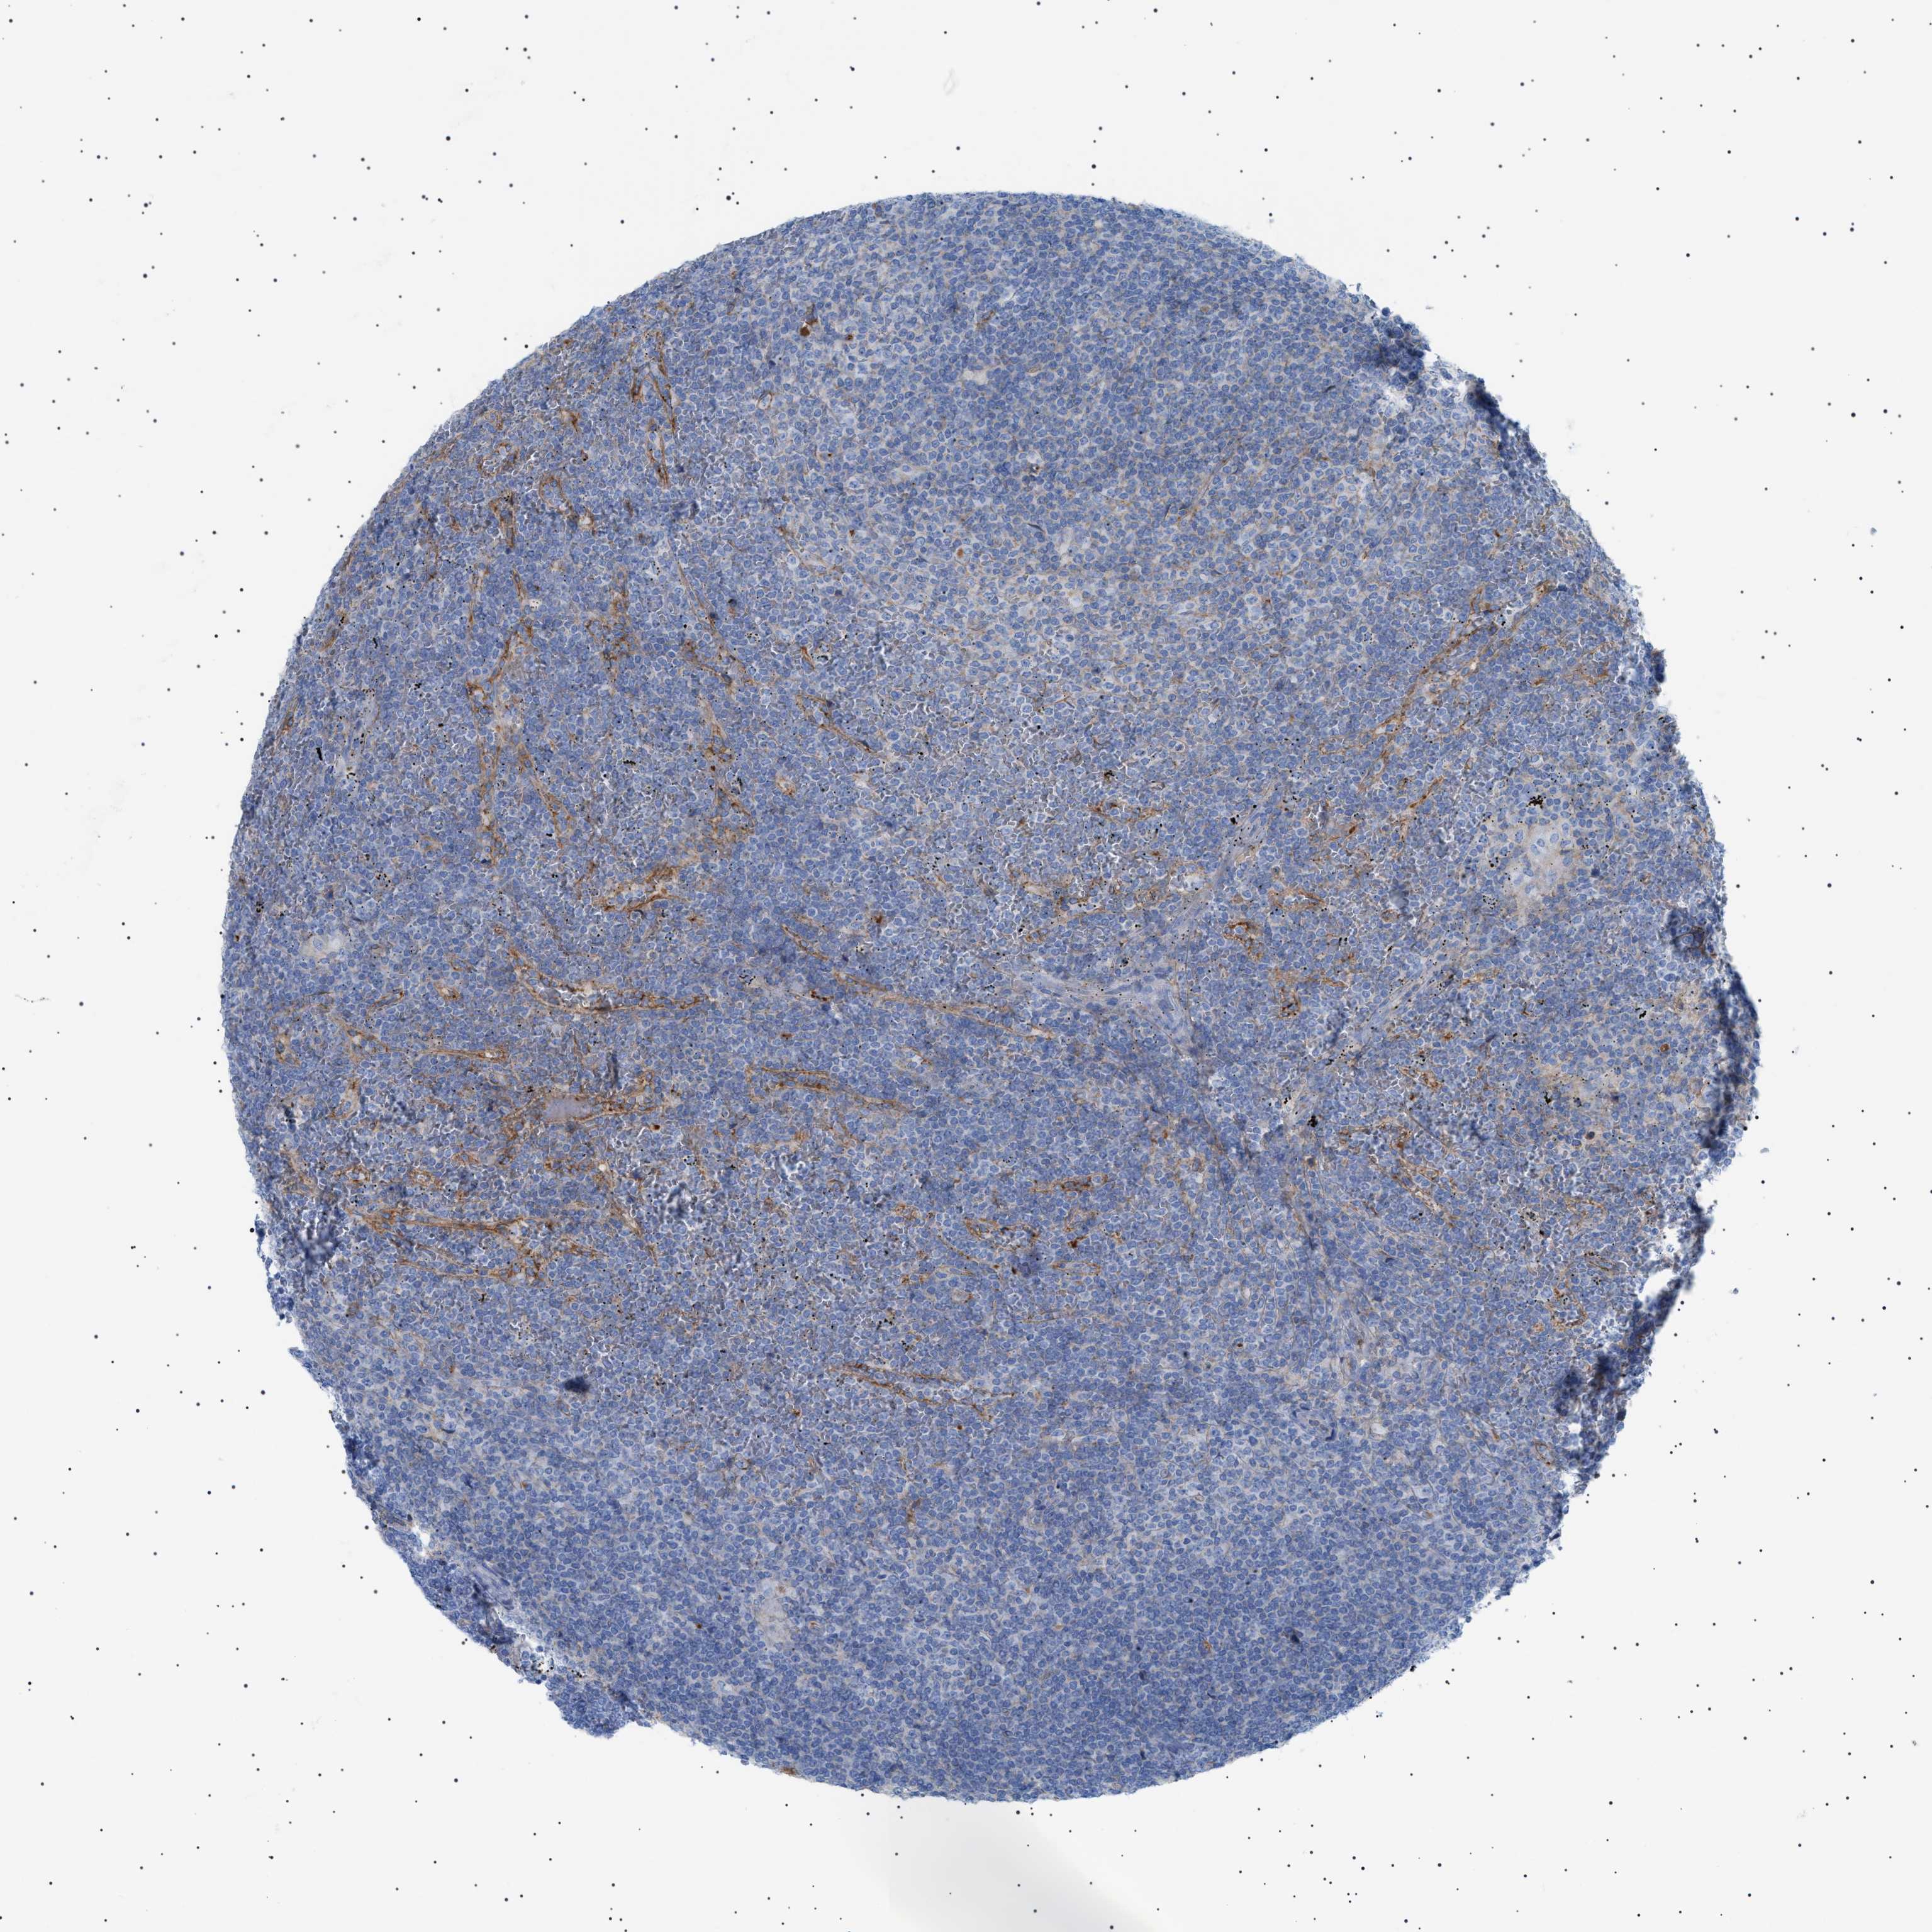

LYMPHOMA - Protein expressioni

A mouse-over function shows sample information and annotation data. Click on an image to view it in a full screen mode. Samples can be filtered based on level of antibody staining by selecting one or several of the following categories: high, medium, low and not detected. The assay and annotation is described here.

Antibody stainingi

Antibody staining in the annotated cell types in the current human tissue is reported as not detected, low, medium, or high, based on conventional immunohistochemistry profiling in selected tissues. This score is based on the combination of the staining intensity and fraction of stained cells.

Each image is clickable and will lead to virtual microscopy that enables deeper exploration of all samples and also displays staining intensity scores, fraction scores and subcellular localization as well as patient and tissue information for each sample.

Antibody HPA060604

Antibody CAB016072

Staining

High

Medium

Low

Not detected

Intensity

Strong

Moderate

Weak

Negative

Quantity

>75%

75%-25%

<25%

None

Location

Nuclear

Cytoplasmic/membranous

Cytoplasmic/membranous,nuclear

Malignant lymphoma, non-Hodgkin's type, Low grade

Malignant lymphoma, non-Hodgkin's type, High grade

Hodgkin's disease, NOS